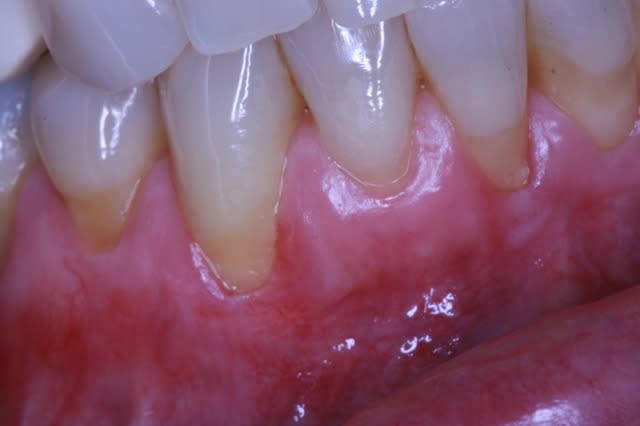

cas un peu plus détérioré... épithélio-conjonctif aurais été préférable?

Pr  op 001 ncozkn - Eugenol

Pre op greffe 002 vmfrhj - Eugenol